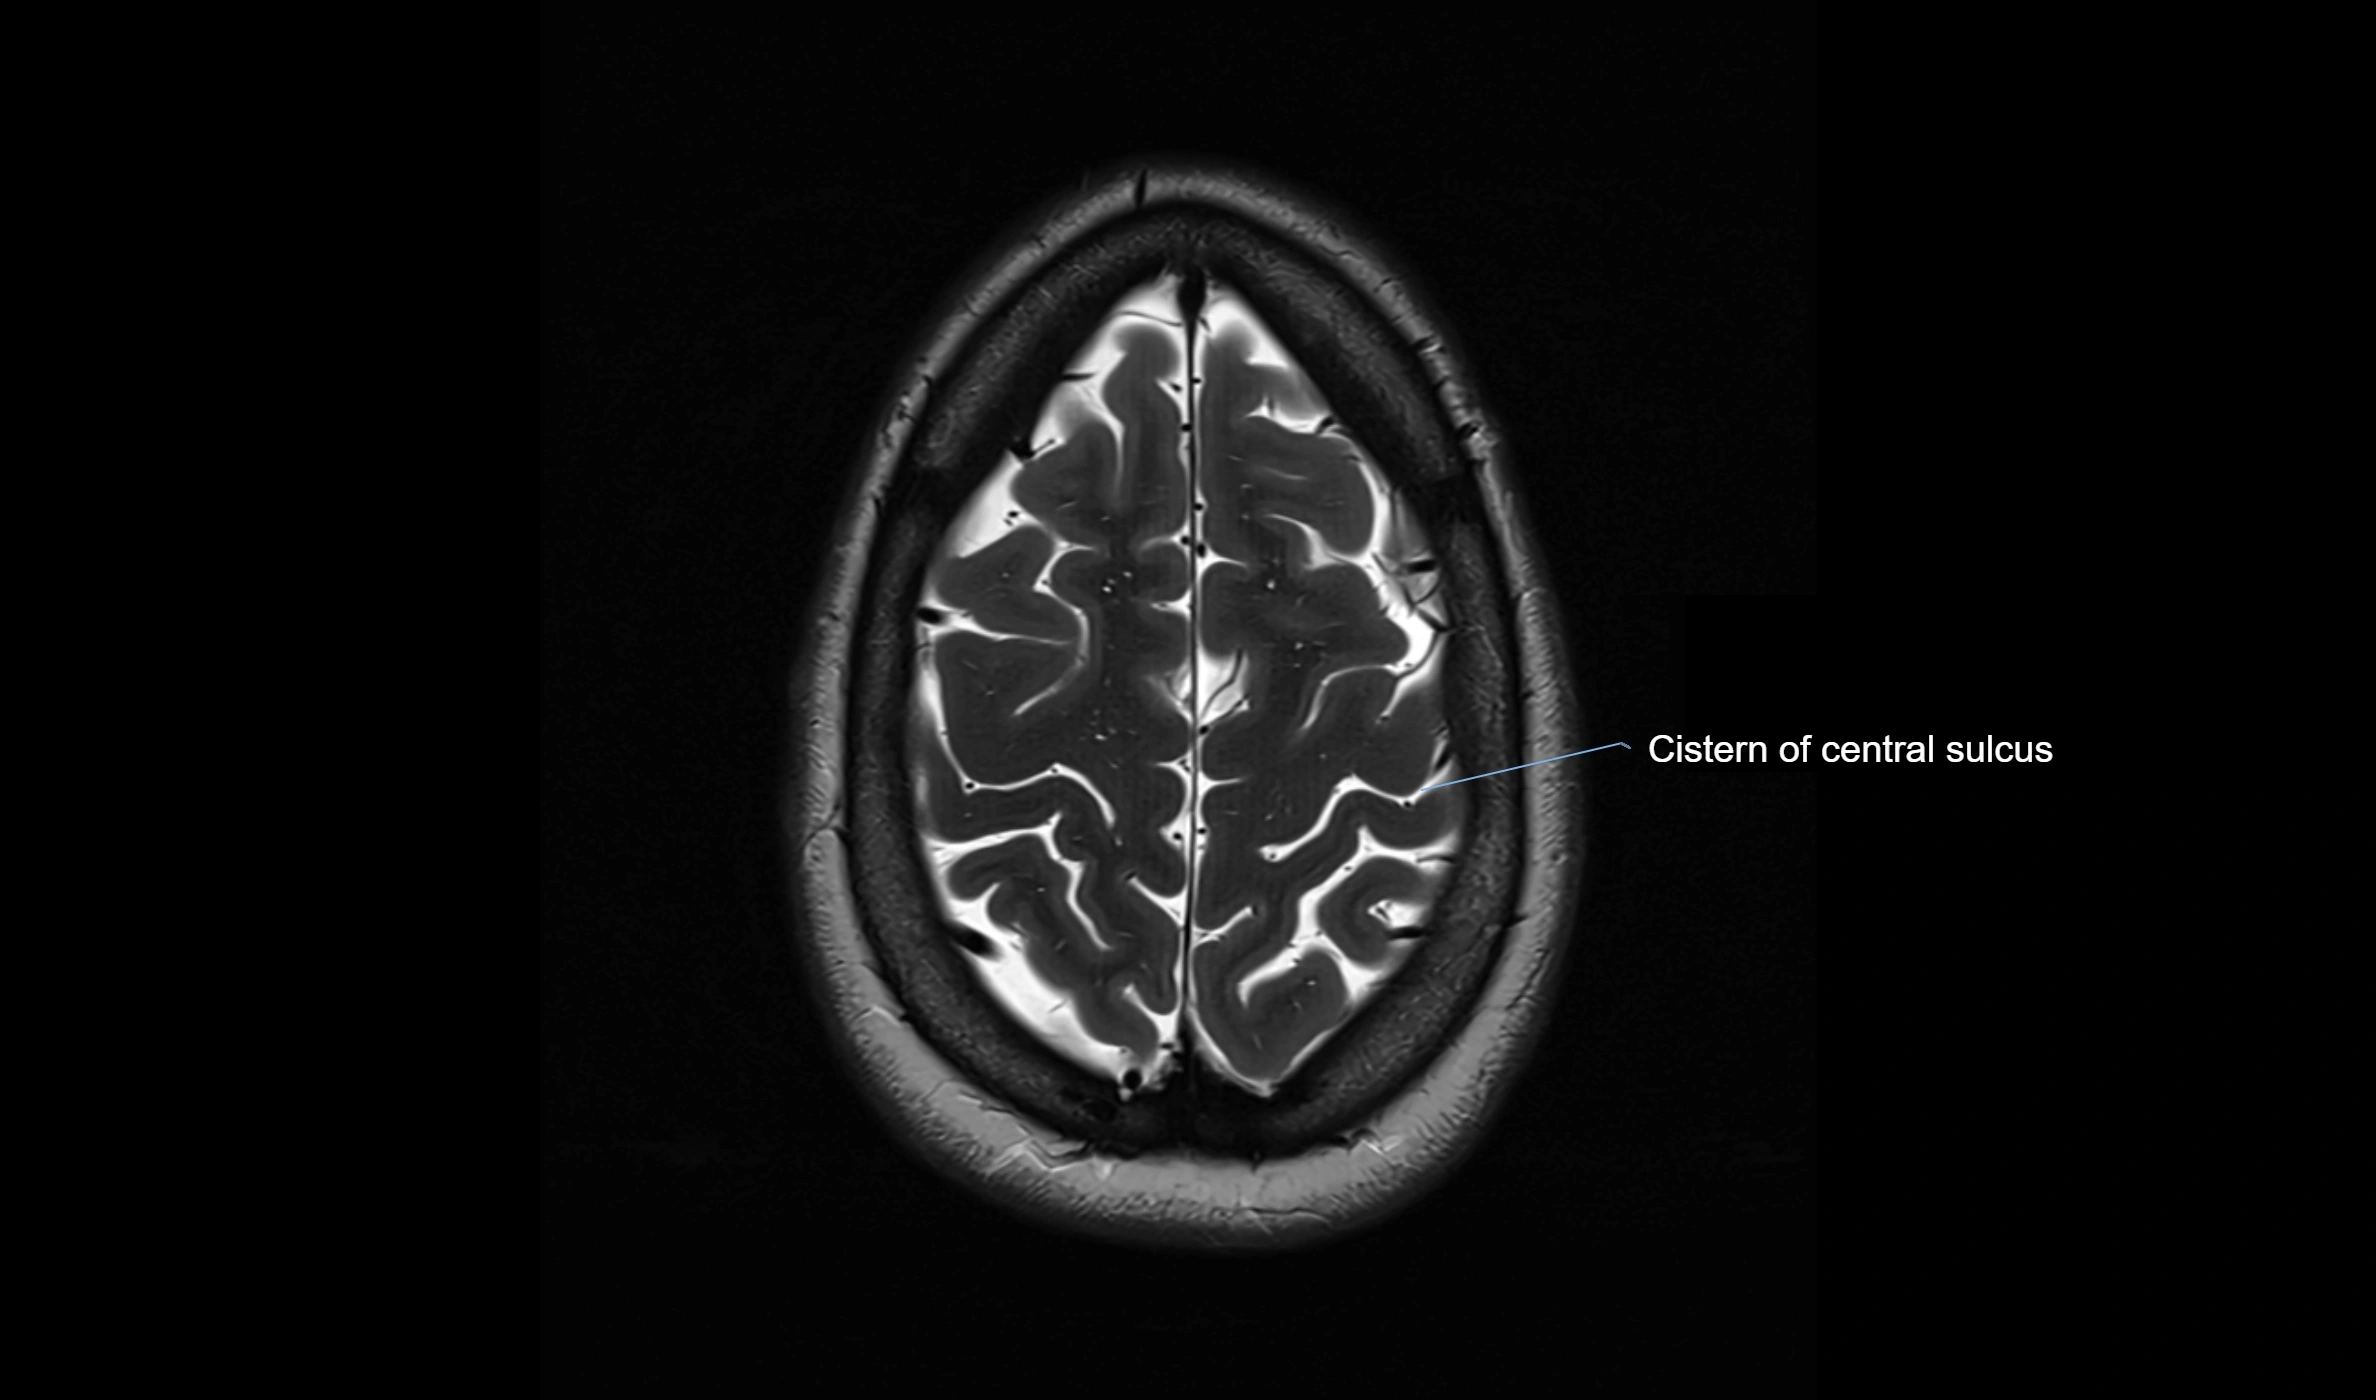

MRI images

image